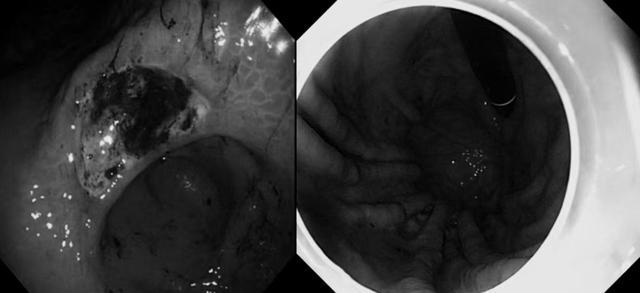

接诊医师怀疑是“胃结石”。经胃镜检查,果然在小张的胃里发现了一块约5.0×5.0厘米的“石头”,它不断摩擦柔软的胃壁,导致多处溃疡。消化内镜中心麻张亮主治医师迅速带领团队为小张实施了“胃镜下碎石并取石术”。手术顺利,结石被成功取出,小张的腹痛症状明显缓解。术后继续抗溃疡治疗,几天后康复出院。

回想这次经历,小张后悔不已,感叹平时要是多了解一些健康科普知识,就不会因一时贪嘴而遭罪了。内镜中心刘元主任介绍,“胃结石”并非罕见病例,常因进食某些物质后在胃内形成既不能被消化又不能及时排出的凝固物或硬块。这些结石在胃内反复摩擦胃壁,不仅会引起疼痛,还可能导致胃糜烂、溃疡、出血、穿孔、肠梗阻等严重后果。